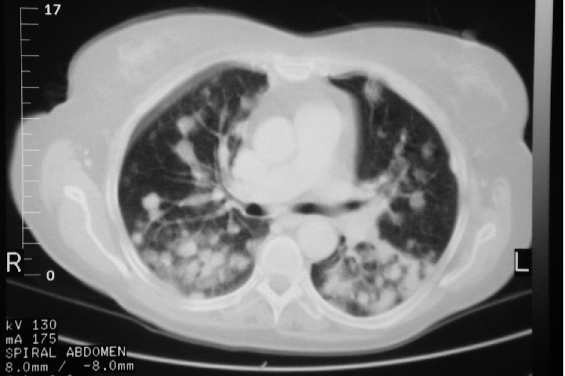

The stage of lymphoma describes the extent of spread of the tumor using the roman numerals i, ii, iii, or iv (1 through 4). B cell non-Hodgkin’s lymphoma of the trachea mimicking COPD | Thorax

B cell non-Hodgkin’s lymphoma of the trachea mimicking COPD | Thorax from thorax.bmj.com